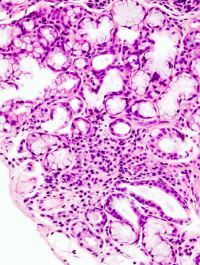

Il linfoma Non HodgKin (LNH) è causato da una eccessiva proliferazione di linfociti, cellule del sistema immunitario. La malattia si sviluppa dai linfonodi per poi diffondersi attraverso il sistema linfatico. Esiste una forma aggressiva della malattia, LNH aggressivo a cellule B che si sviluppa con rapida crescita e raggiunge gli stadi avanzati molto velocemente. Il […]